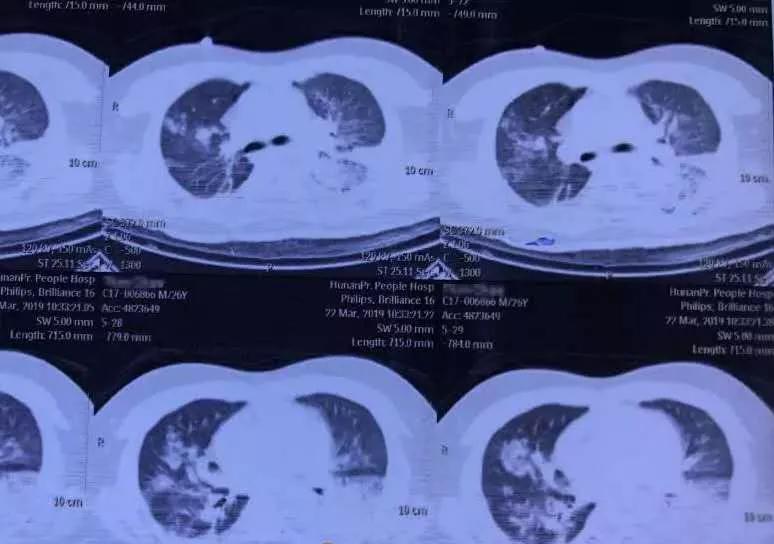

湘西吉首某医院的一名26岁的内科医生田先生,一开始只是出现了流鼻涕、咳嗽和发热的症状,甚至高烧到40℃。

本以为只是普通的感冒,可吃了感冒药后,病情没有好转,反而越来越严重,在晕倒后,被送去医院。

最后,他被诊断为 “重症肺炎,多脏器功能衰竭” 。虽然一直在治疗,可他还是开始神志不清,生命危在旦夕。

后来,医院成立了专家小组,确诊田先生为: 重症腺病毒肺炎。

医院随后制定了一套治疗方案,终于帮田先生挺过了这一关。

医生解释说, 因为腺病毒肺炎早期症状和普通肺炎很相似,所以很容易被忽视,而这非常容易对孩子造成致命性的伤害。